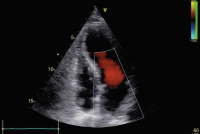

Fallbericht: Tako-Tsubo-Syndrom: Thromboembolierisiko in der Frühphase vielleicht unterschätzt?

Journal für Kardiologie - Austrian Journal of Cardiology 2020; 27 (9-10): 344-345 Volltext (PDF) Abbildungen mit Filmsequenzen